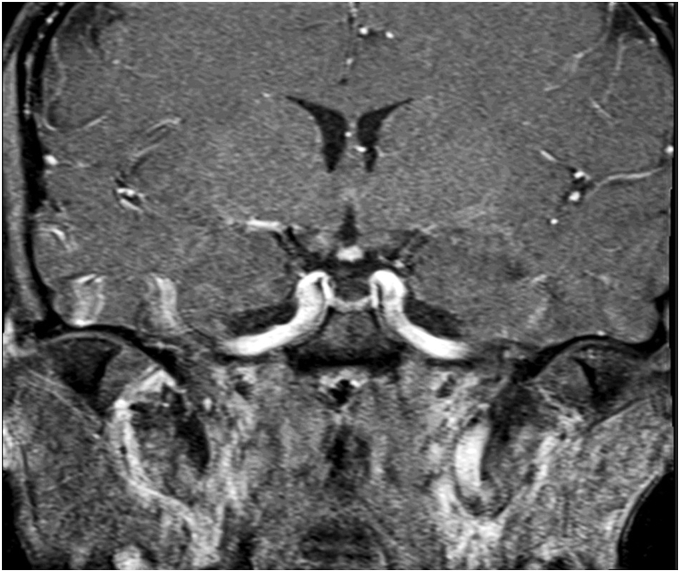

A 42-year-old-female presented for evaluation of premature menopause, weight loss, and occasional dizziness. On examination she had short stature and absent secondary sexual features. Laboratory tests were consistent with hypopituitarism with follicle stimulating hormone 0.5 mIU/mL (16.7-113); luteinizing hormone 1.2 mIU/mL (10.8-58.6); prolactin 10.4 ng/mL (2.7-19.6); estradiol 20 pg/mL; cortisol 2 mcg/dL (6.7-22.6); adrenocorticotropic hormone 18 pg/mL (6-50); thyroid stimulating hormone 10.33 uIU/mL (0.28-3.8); free T4 0.41 ng/dL (0.58-1.64); insulin like growth factor-1 −3.7 SD (17 ng/mL) (52-328); and adrenocorticotropic hormone stimulation confirmed secondary adrenal insufficiency. The magnetic resonance imaging of the brain revealed an ectopic posterior pituitary with a partially empty sella, absence of the pituitary stalk, and a small anterior pituitary. The patient was initiated on replacement hormones with improvement in her symptoms.